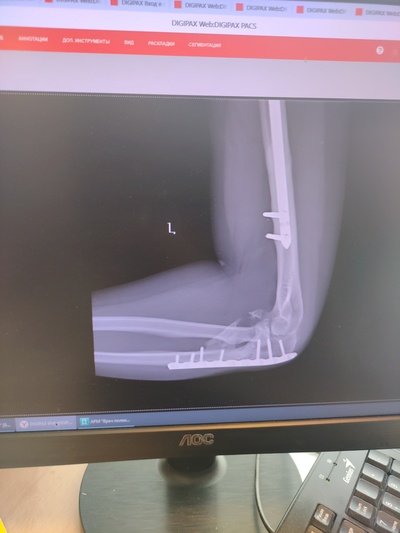

Устройство руки представляете себе? Есть плечевая кость, есть локтевой сустав, в него входят две кости - локтевая и лучевая. Я сломал обе. Локтевой сустав цел, но окончания лучевой и локтевой кости - в щепки. Просто в много мелких острых щепок. Вместо предплечья теперь - бесполезный окорок, который висит только на сухожилиях. Называл его ласково - "моя рулька".

Короче, две кости соединили железкой и вставили в сустав. Одну головку кости (видимо лучевой) выкинули нахрен, собаки были довольны.